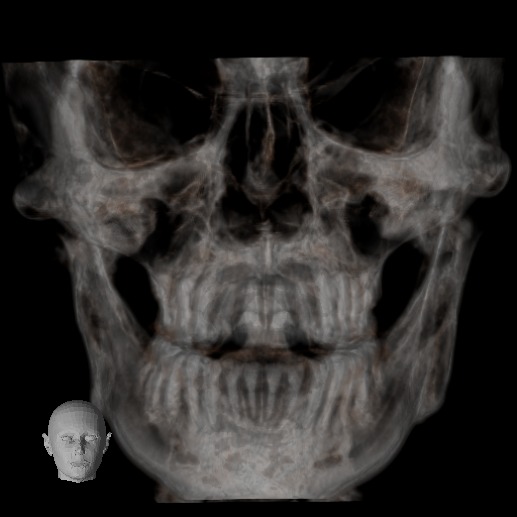

El Centro Radiológico Diagnóstico Oral 3D, es una empresa antioqueña que ofrece a sus pacientes desde el año 2009, tecnología de vanguardia en radiografías tridimensionales con calidad fotográfica. Las posibilidades para mejorar la eficacia en los diagnósticos bucales son evidentes, también lo son las posibilidades de manipulación de imagen. El sistema de imágenes en 3D ofrece detalles sin precedentes, convirtiéndola en la opción idónea para la mayoría de aplicaciones odontológicas, incluyendo implantes, tratamiento de conductos, ortodoncia, odontopediatría, periodoncia y cirugía

El mayor beneficiado con el uso de esta tecnología es el paciente, el cual podrá ser evaluado en todas sus dimensiones con una baja dosis de radiación, con un costo accesible y sin contaminar  el medio ambiente. Dependiendo de la necesidad del paciente, hay varios tipos de tomografías y los especialistas en el área odontológica hacen uso de ellas según su especialidad.

Evaluación de patologías dentales y maxilofaciales

Diagnóstico de traumatismos dentales y maxilofaciales

Detección de lesiones quísticas y tumorales